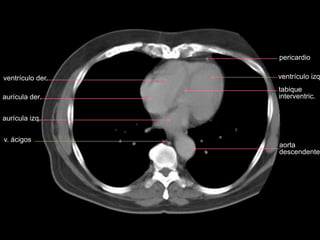

ventrículo der.

aurícula izq.

v. ácigos

aurícula der.

aorta

descendente

ventrículo izq

tabique

interventric.

pericardio

ventríc. izq.

E